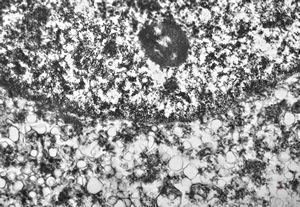

poxvirus - molluscum contagiosum